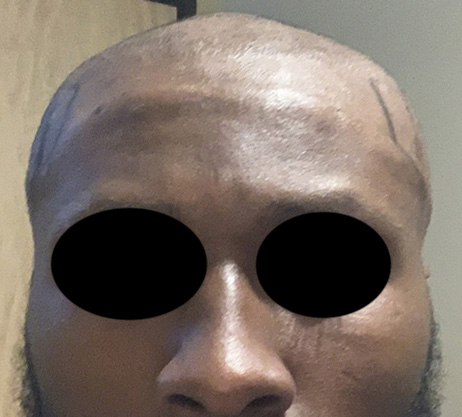

Patient 100

Desire for reshaping of an asymmetric flat back of the head in a shaved head male.

A combined back of the head reshaping procedure was done with a custom skull implant, sagittal ridge reduction and a right temporal muscle reduction.

Desire for reshaping of an asymmetric flat back of the head in a shaved head male.

A combined back of the head reshaping procedure was done with a custom skull implant, sagittal ridge reduction and a right temporal muscle reduction.